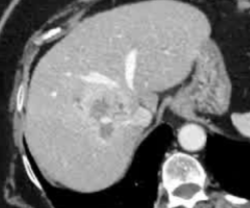

· 单中心、样本量小; 83 岁的女性,体重超标 40 毫米单发 ICC(S7-S8) 中肝静脉和右肝静脉浸润性,活检:非酒精性脂肪性肝炎(慢性肝病),马斯氏(MaS)病(30%)

考虑采用“三步策略 TARE→ PVE → Surgery”方案 剂量活性:1.56 和 3.16 GBq